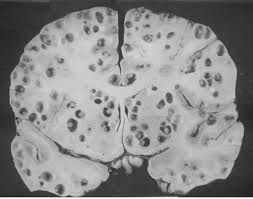

Dos tipos de quistes:

Quiste celuloso, con forma ovalada o redondeada, que suele encontrarse en el parénquima cerebral (3-20 mm)

Quiste celuloso, en áreas corticales del SNC y ganglios basales.